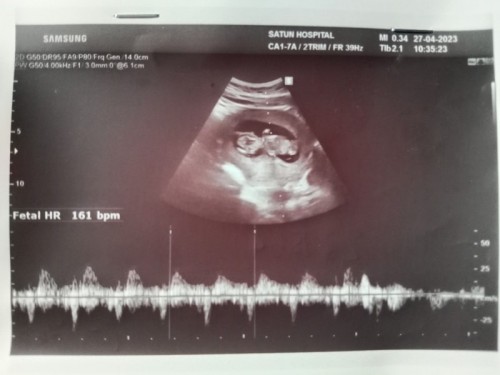

อยากทราบค่ะ พอดีท้อง 13w+ 3d อยากทราบว่าท้องออกแล้วยังคะแล้วแม่ๆคนไหนรู้สึกมั้ยคะ พอดีบ้านนี้ไปซาวด์มาหมอบอกเสียงหัวใจน้องปกติและน้องดิ้นยุ่ด้วยแต่ทำไมแม่ไม่รู้สึกเลยคะ หรือเป็นเพราะท้องอ่อนยุ่คะและช่วงนี่ก็ปวดท้องน้อยมากๆเลยคะร้าวไปถึงหลังเลยเป็นเพราะอะไรคะ #ขอบคุณล่วงหน้านะคะ #ท้องแรก